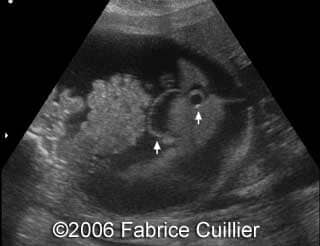

Postnatal image of the baby

At 37 week of pregnancy, a cesarean section was performed. Female baby was born weighting 5.1 kg wit the Apgar scores 1/1/1. The baby was referred to intensive care unit. The newborn’s abdomen was distended due to bilateral kidney’s enlargement. Postnatal scans confirmed prenatal findings of bilateral kidney’s enlargement. Renal and hepatic functions were abnormal. A puncture of the ascites was performed (>0.5 l), but anuria appeared after that. Despite of intensive neonatal care, the baby died on the first postnatal day due to circulatory collapse and respiratory distress. Parents refused the postmortem examination, but the kidney biopsy was done with the diagnosis of nephroblastomatosis.

Our final diagnosis was Perlman syndrome.